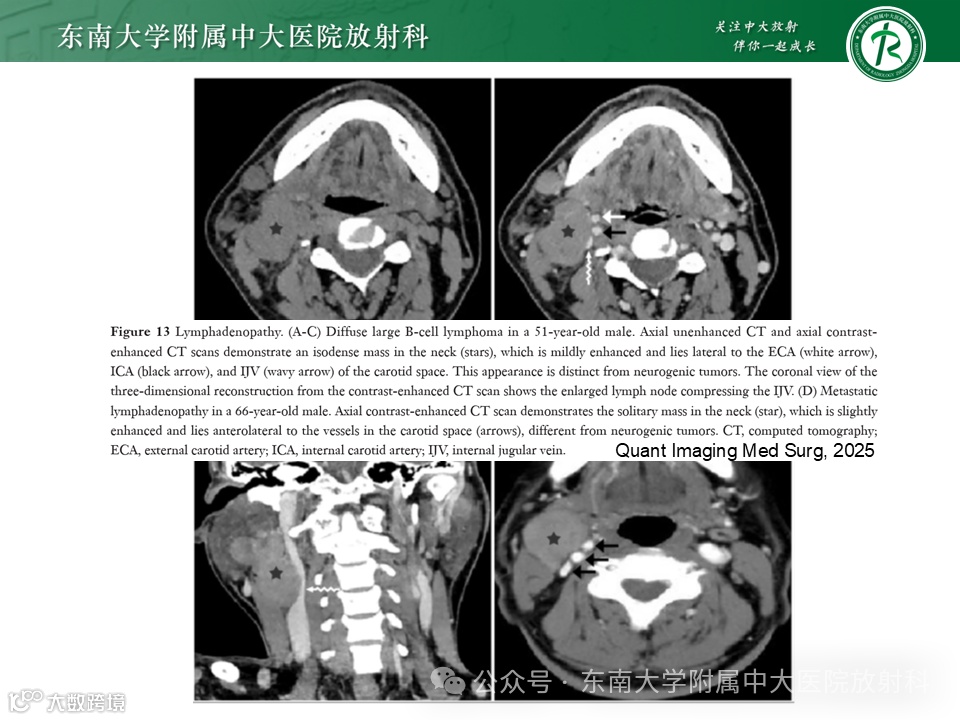

病例1.3:右侧多灶性淋巴瘤伴融合,咽旁、咽后及颈动脉间隙受侵